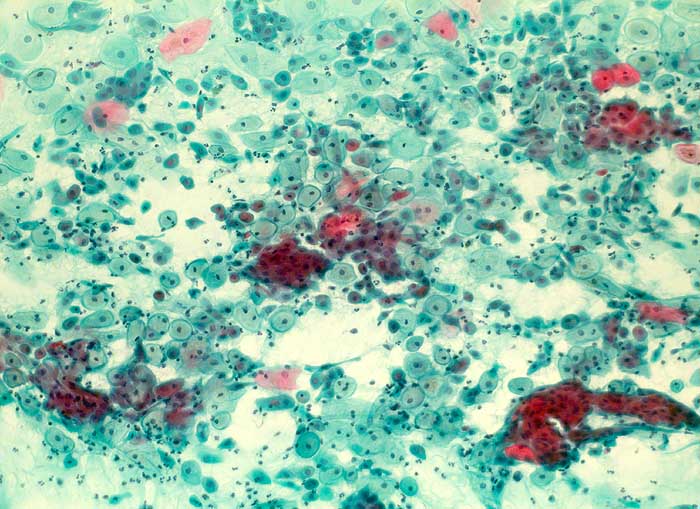

Wegen des postpartalen Abfalls der Progesteronproduktion enthält der Abstrich bis zum Einsetzen des normalen Zyklus glykogenreiche polygonale Parabasalzellen, die als "Post-partum-Zellen" bezeichnet werden.